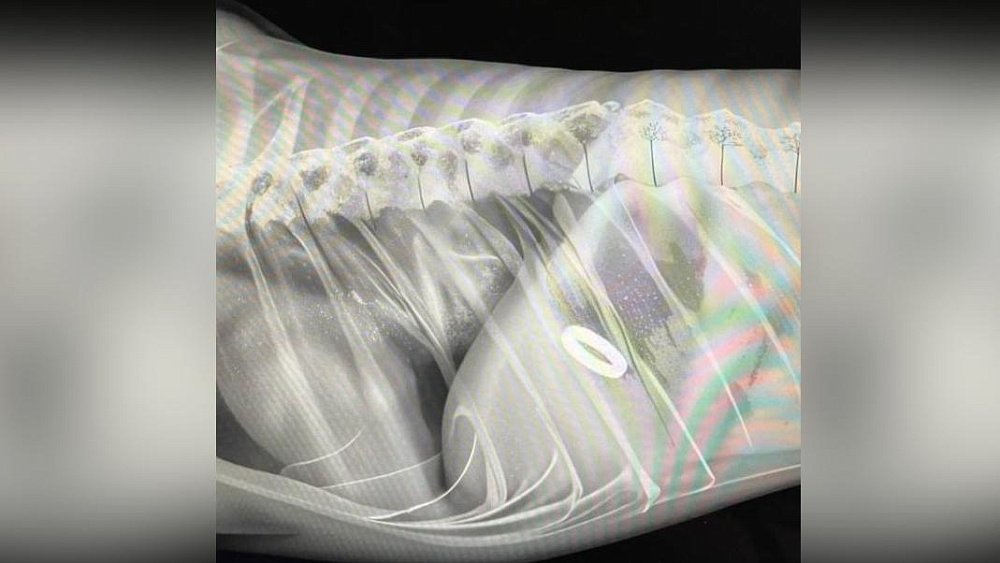

Забавная история произошла в Челябинске прямо в День всех влюбленных. Молодой человек купил кольцо, чтобы в праздничный день сделать своей подруге предложение. Но все пошло не по плану: его пес Беляш случайно проглотил украшение. Пришлось везти животное к ветеринару. Однако помолвка не сорвалась, а стала по-настоящему запоминающейся.

По пути в ветеринарную клинику парень придумал, как сделать предложение руки и сердца незабываемым. И, прибыв в лечебницу, попросил доктора в справке написать специальную рекомендацию для жениха. Подробнее об этой истории рассказали наши коллеги из издания «Челябинск сегодня».